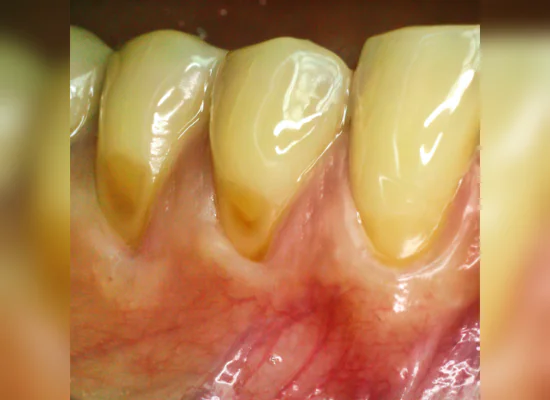

Stained and Discolored/Yellowed Teeth

It is inevitable that we will all experience yellowing of our teeth due to the normal ageing process. This is because of the outer enamel layer wearing out and the inner yellower layer showing through. Add to this years of food/beverage consumption, social habits such as smoking/coffee/tea/wines, we will then end up with a yellower shade painted over our teeth.

External stains (Chromogenic stains)

Result from social habits such as tobacco smoking, drinks with high colouration and foods with deep pigmentation. Generally these stains can be removed with the following techniques – air polishing, microabrasion and whitening with peroxide agents.

Internal Stains

Arise from a change in the shade of the deep layer of the tooth known as the sensitive dentine layer. Common causes of such stains are from silver amalgam fillings, root canal fillings, exposure to high concentrations to fluoride at a certain time (young patients who accidentally ingest fluoride toothpastes), high dose antibiotics for young patients, dental trauma and rare dental genetic conditions such as amelogenesis imperfecta. Suitable treatments can be combination of whitening, veneers and or dental crowns.